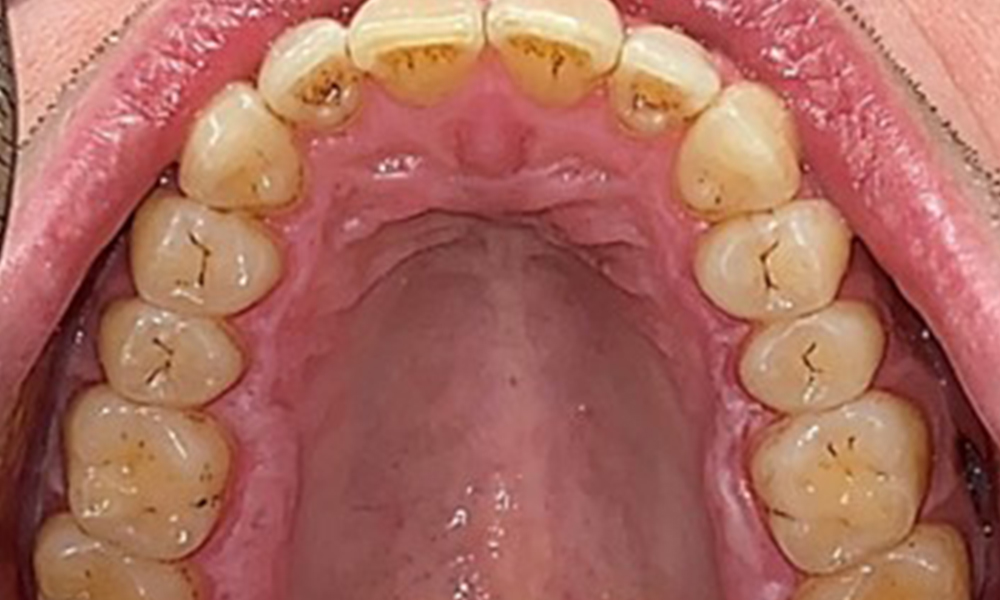

Дентални резултати

Пациентът има пълно съзъбие с общо 28 зъба. Налице са забележими ерозии и атриции. (Фиг. 4, Фиг. 5). Поради бруксизъм пациентът е носил шина с коригиран блок на захапката през нощта в продължение на много години. Ерозиите са причинени от продължителна консумация на изотонични напитки. Не сe наблюдава загуба на пародонтална кост или активни кариозни лезии.